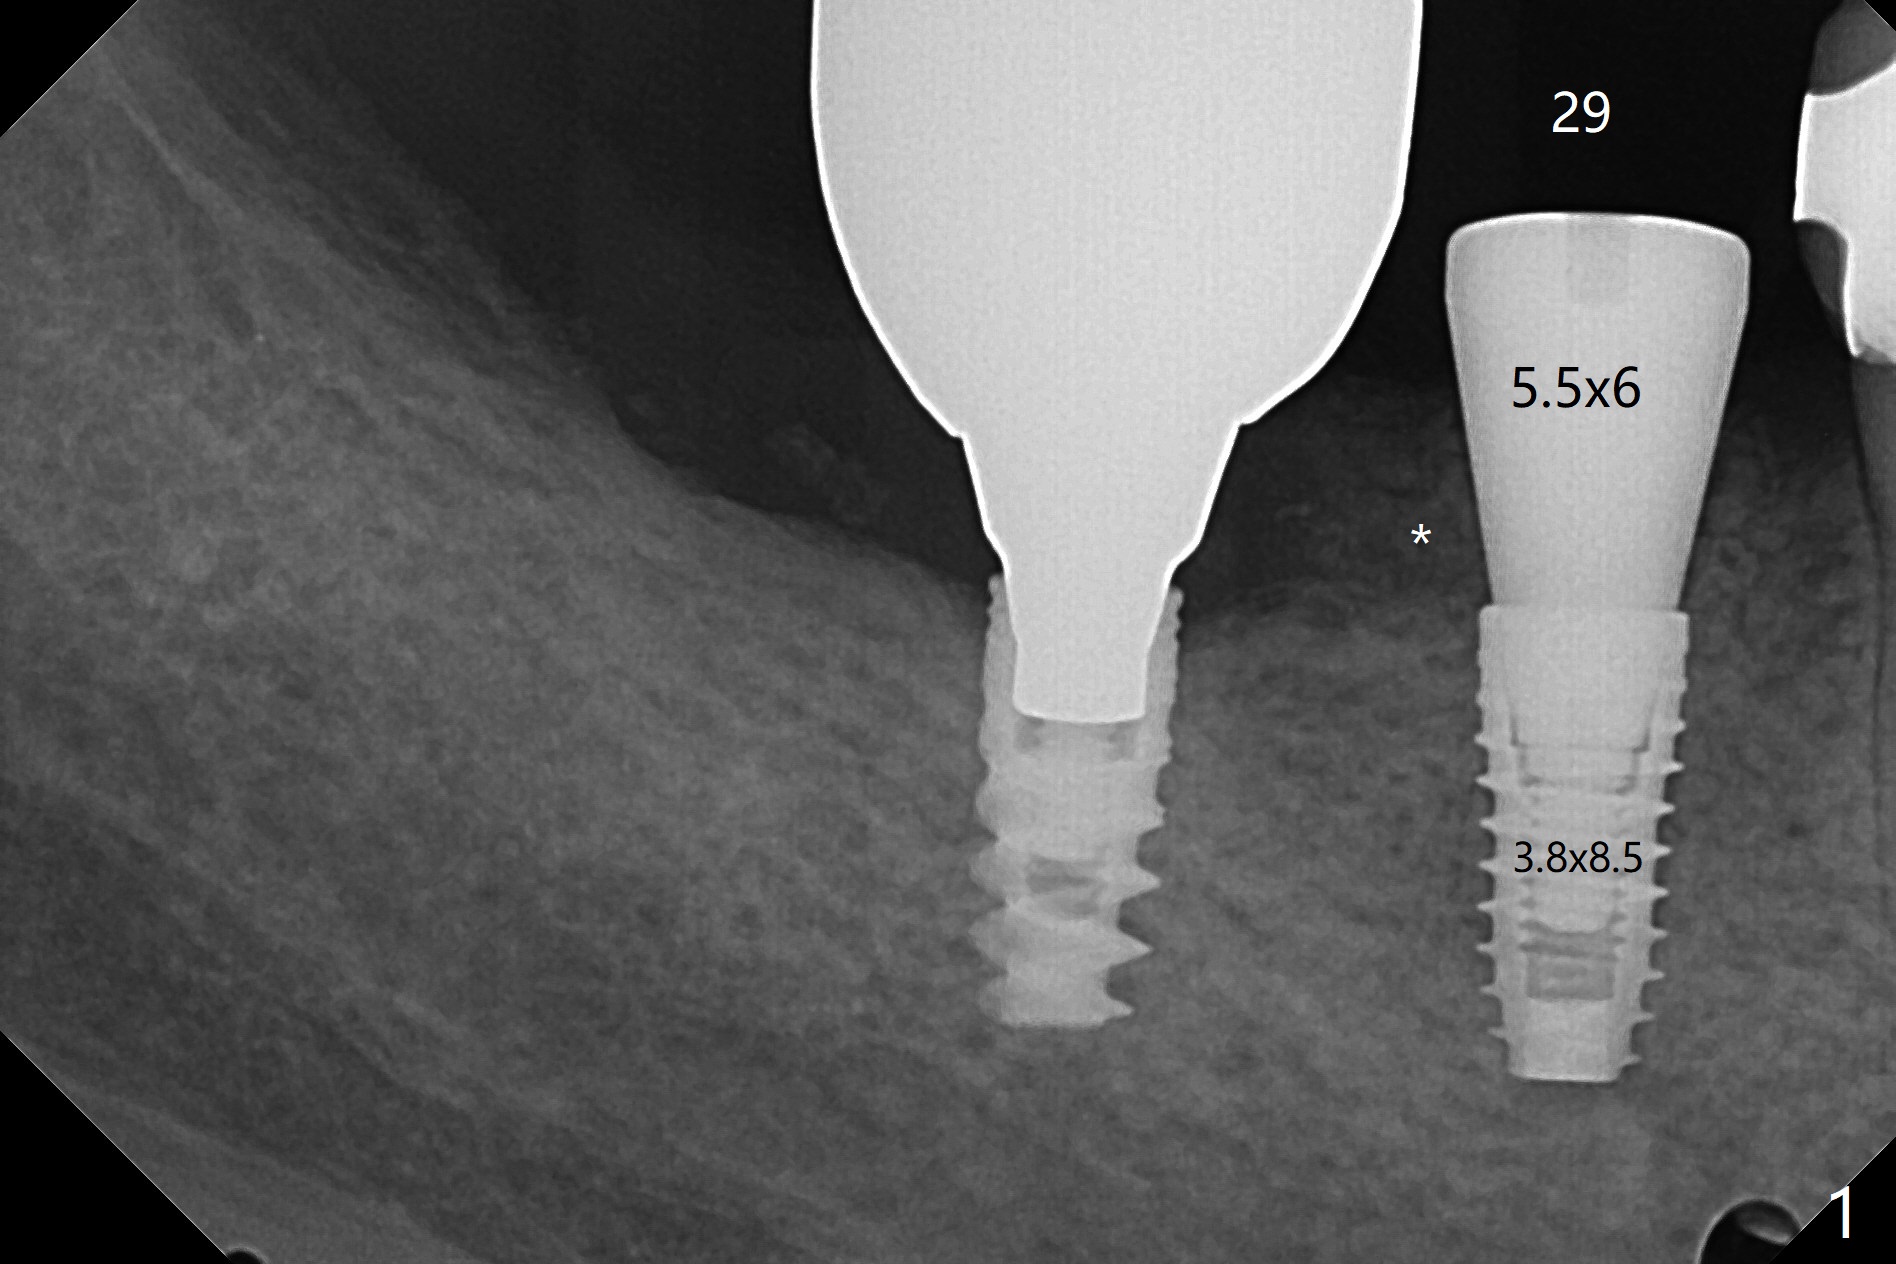

术前检查植牙位点角化龈,好像不太成熟(23,29号牙位点保存2个月,26号牙4个月),所以切开。翻瓣后,放置导板,29号牙位有意减少钻洞直径,用完3毫米钻头后,颊侧骨板已经薄,因此放入3.8x8.5毫米植体(设计4.5x8.5),颊侧植体顶端略微暴露,种深0.5毫米,之后颊侧放置自体骨和异体骨(图一:*)。26号牙钻洞也偏颊侧,所以选择4毫米袖的一段式植体,可以种深(图二,与图三对比),植入自体骨后,使用胎盘膜覆盖。由于没有特别一段式植体导板钻头,最细钻头2.2毫米,所以扭力低,没有即刻修复,下次应该减少钻洞深度,增加扭力。